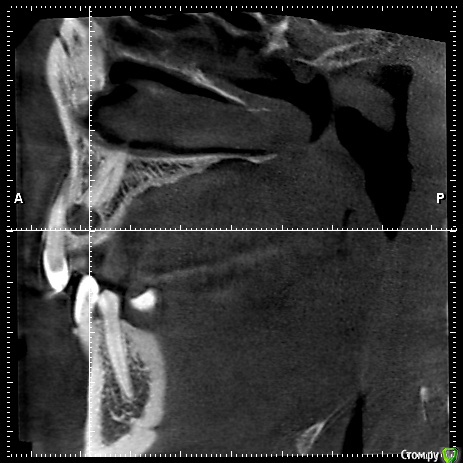

natalie_summerwhile Опубликовано 10 июля, 2017 Автор Поделиться Опубликовано 10 июля, 2017 Во рту вместо клыка молочный Ссылка на комментарий